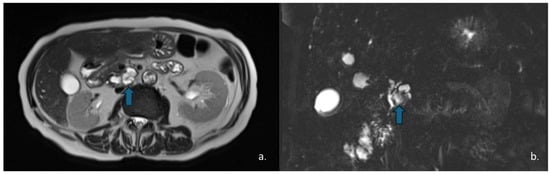

Pancreatic Cystic Lesions: From Basic Knowledge to Recent Guidelines

Pancreatic cystic lesions (PCLs) are increasingly detected due to widespread use of cross-sectional imaging. They encompass a heterogeneous group of lesions, ranging from benign pseudocysts and serous cystic neoplasms (SCNs) to premalignant mucinous cystic neoplasms (MCNs) and intraductal papillary mucinous neoplasms (IPMNs), as [...] Read more.

Pancreatic cystic lesions (PCLs) are increasingly detected due to widespread use of cross-sectional imaging. They encompass a heterogeneous group of lesions, ranging from benign pseudocysts and serous cystic neoplasms (SCNs) to premalignant mucinous cystic neoplasms (MCNs) and intraductal papillary mucinous neoplasms (IPMNs), as well as rare malignant entities such as solid pseudopapillary epithelial neoplasm (SPENs) and cystic pancreatic neuroendocrine tumors (cystic PanNETs). Management of PCLs depends on their malignant potential; therefore, an accurate classification is essential for optimizing treatment. This narrative review summarizes current knowledge on the epidemiology, imaging characteristics, diagnosis, and management of PCLs, highlighting the role of CT, MRI, MRCP, and endoscopic ultrasound. Recent advances in radiomics for lesion characterization and risk stratification, particularly in IPMNs, are discussed. Full article

Show Figures

Figure 1